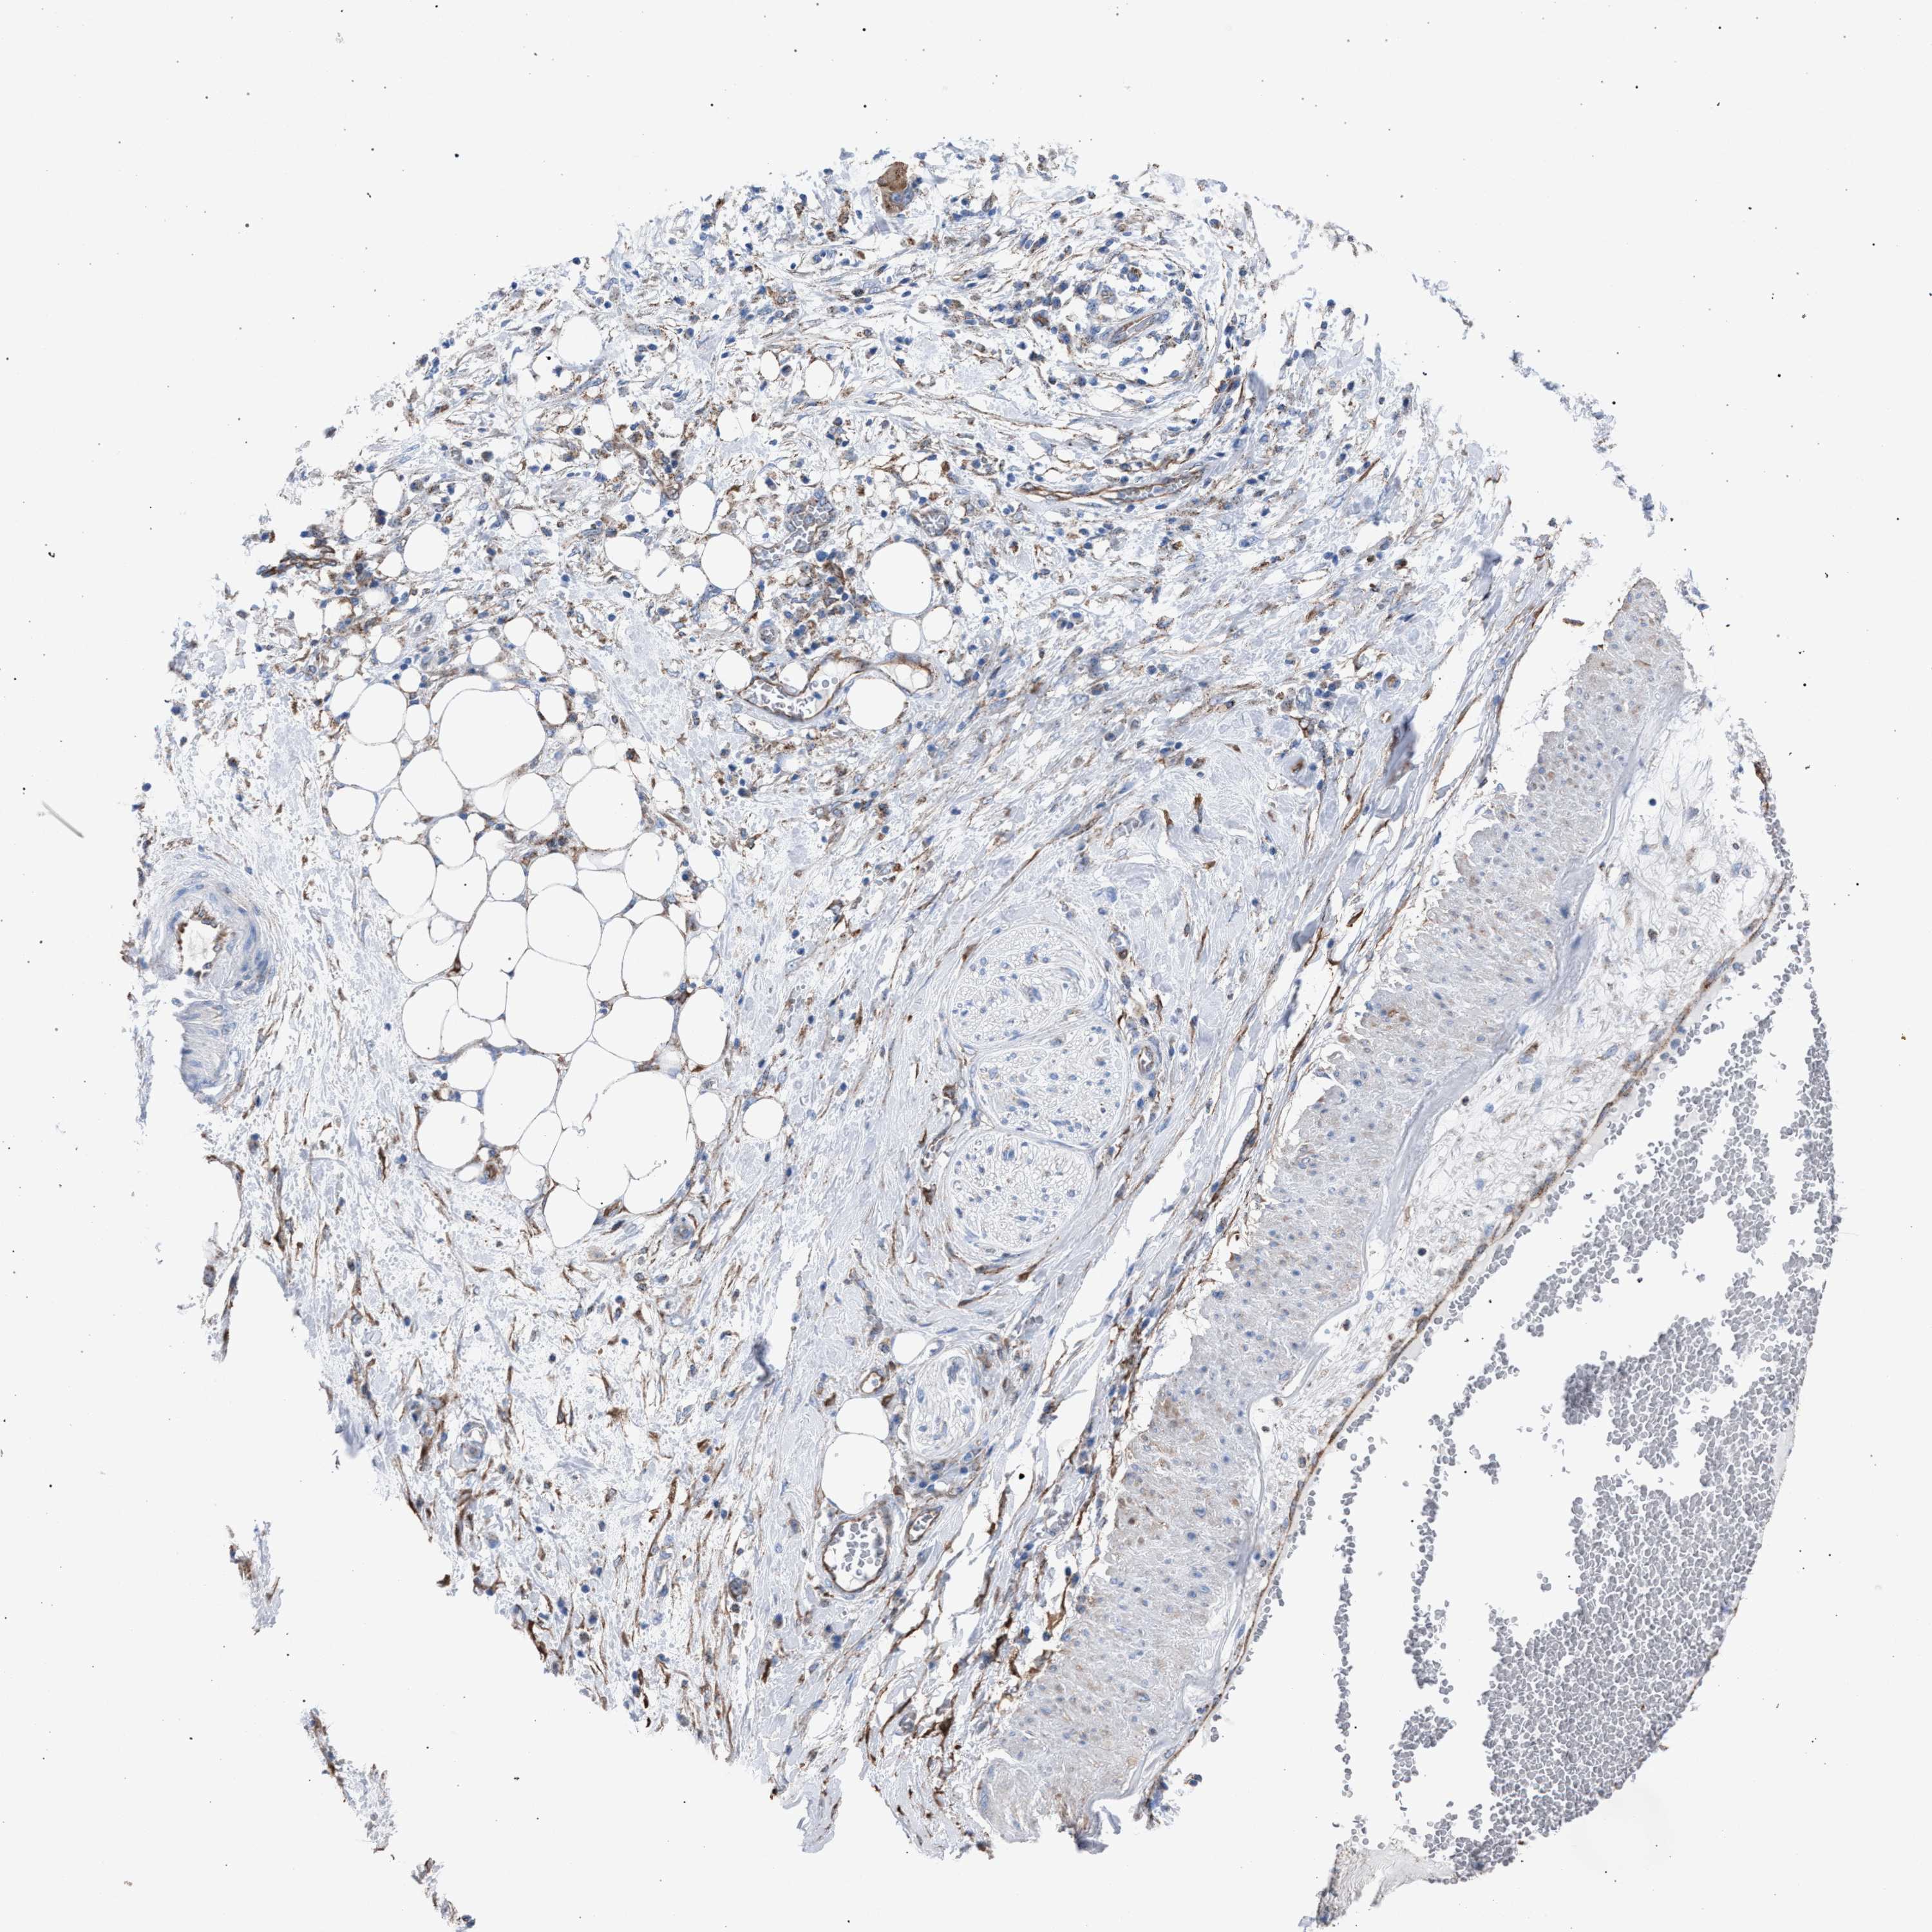

PANCREATIC CANCER - Protein expressioni

A mouse-over function shows sample information and annotation data. Click on an image to view it in a full screen mode. Samples can be filtered based on level of antibody staining by selecting one or several of the following categories: high, medium, low and not detected. The assay and annotation is described here.

Note that samples used for immunohistochemistry by the Human Protein Atlas do not correspond to samples in the TCGA dataset.

Antibody stainingi

Antibody staining in the annotated cell types in the current human tissue is reported as not detected, low, medium, or high, based on conventional immunohistochemistry profiling in selected tissues. This score is based on the combination of the staining intensity and fraction of stained cells.

Each image is clickable and will lead to virtual microscopy that enables deeper exploration of all samples and also displays staining intensity scores, fraction scores and subcellular localization as well as patient and tissue information for each sample.

Antibody HPA021302

Antibody HPA021311

Antibody HPA021479

Adenocarcinoma, NOS